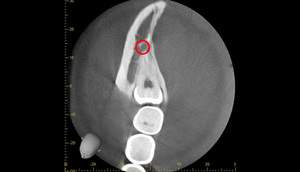

CT画像①

麻布十番歯科での右下の親知らずが真横に生えている症例のCT画像①

CTの1部分の画像です。下歯槽神経と親知らずはほんの少し接触しているような状態でした。リスクなど説明し、2回法で抜いていくことにしました。

2回法とは、その名の通り、2回かけて親知らずを抜いていく方法になります。

1回目は歯の頭の部分だけを切るだけになります。2回目は数ヶ月経ってから行いますが、1回目で頭の部分を取ったスペースに歯が伸びてきますので、下歯槽神経と離れたかを確認してから、根の部分を抜いていく、そういった方法になります。